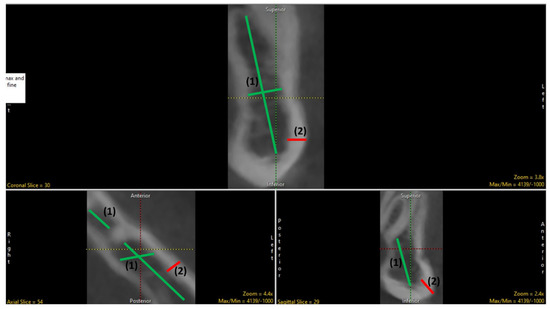

2.1. Selection of Region of Interest (ROI)

2.2. Data Preprocessing

2.3. Segmentation (Manual and Semi-Automatic)